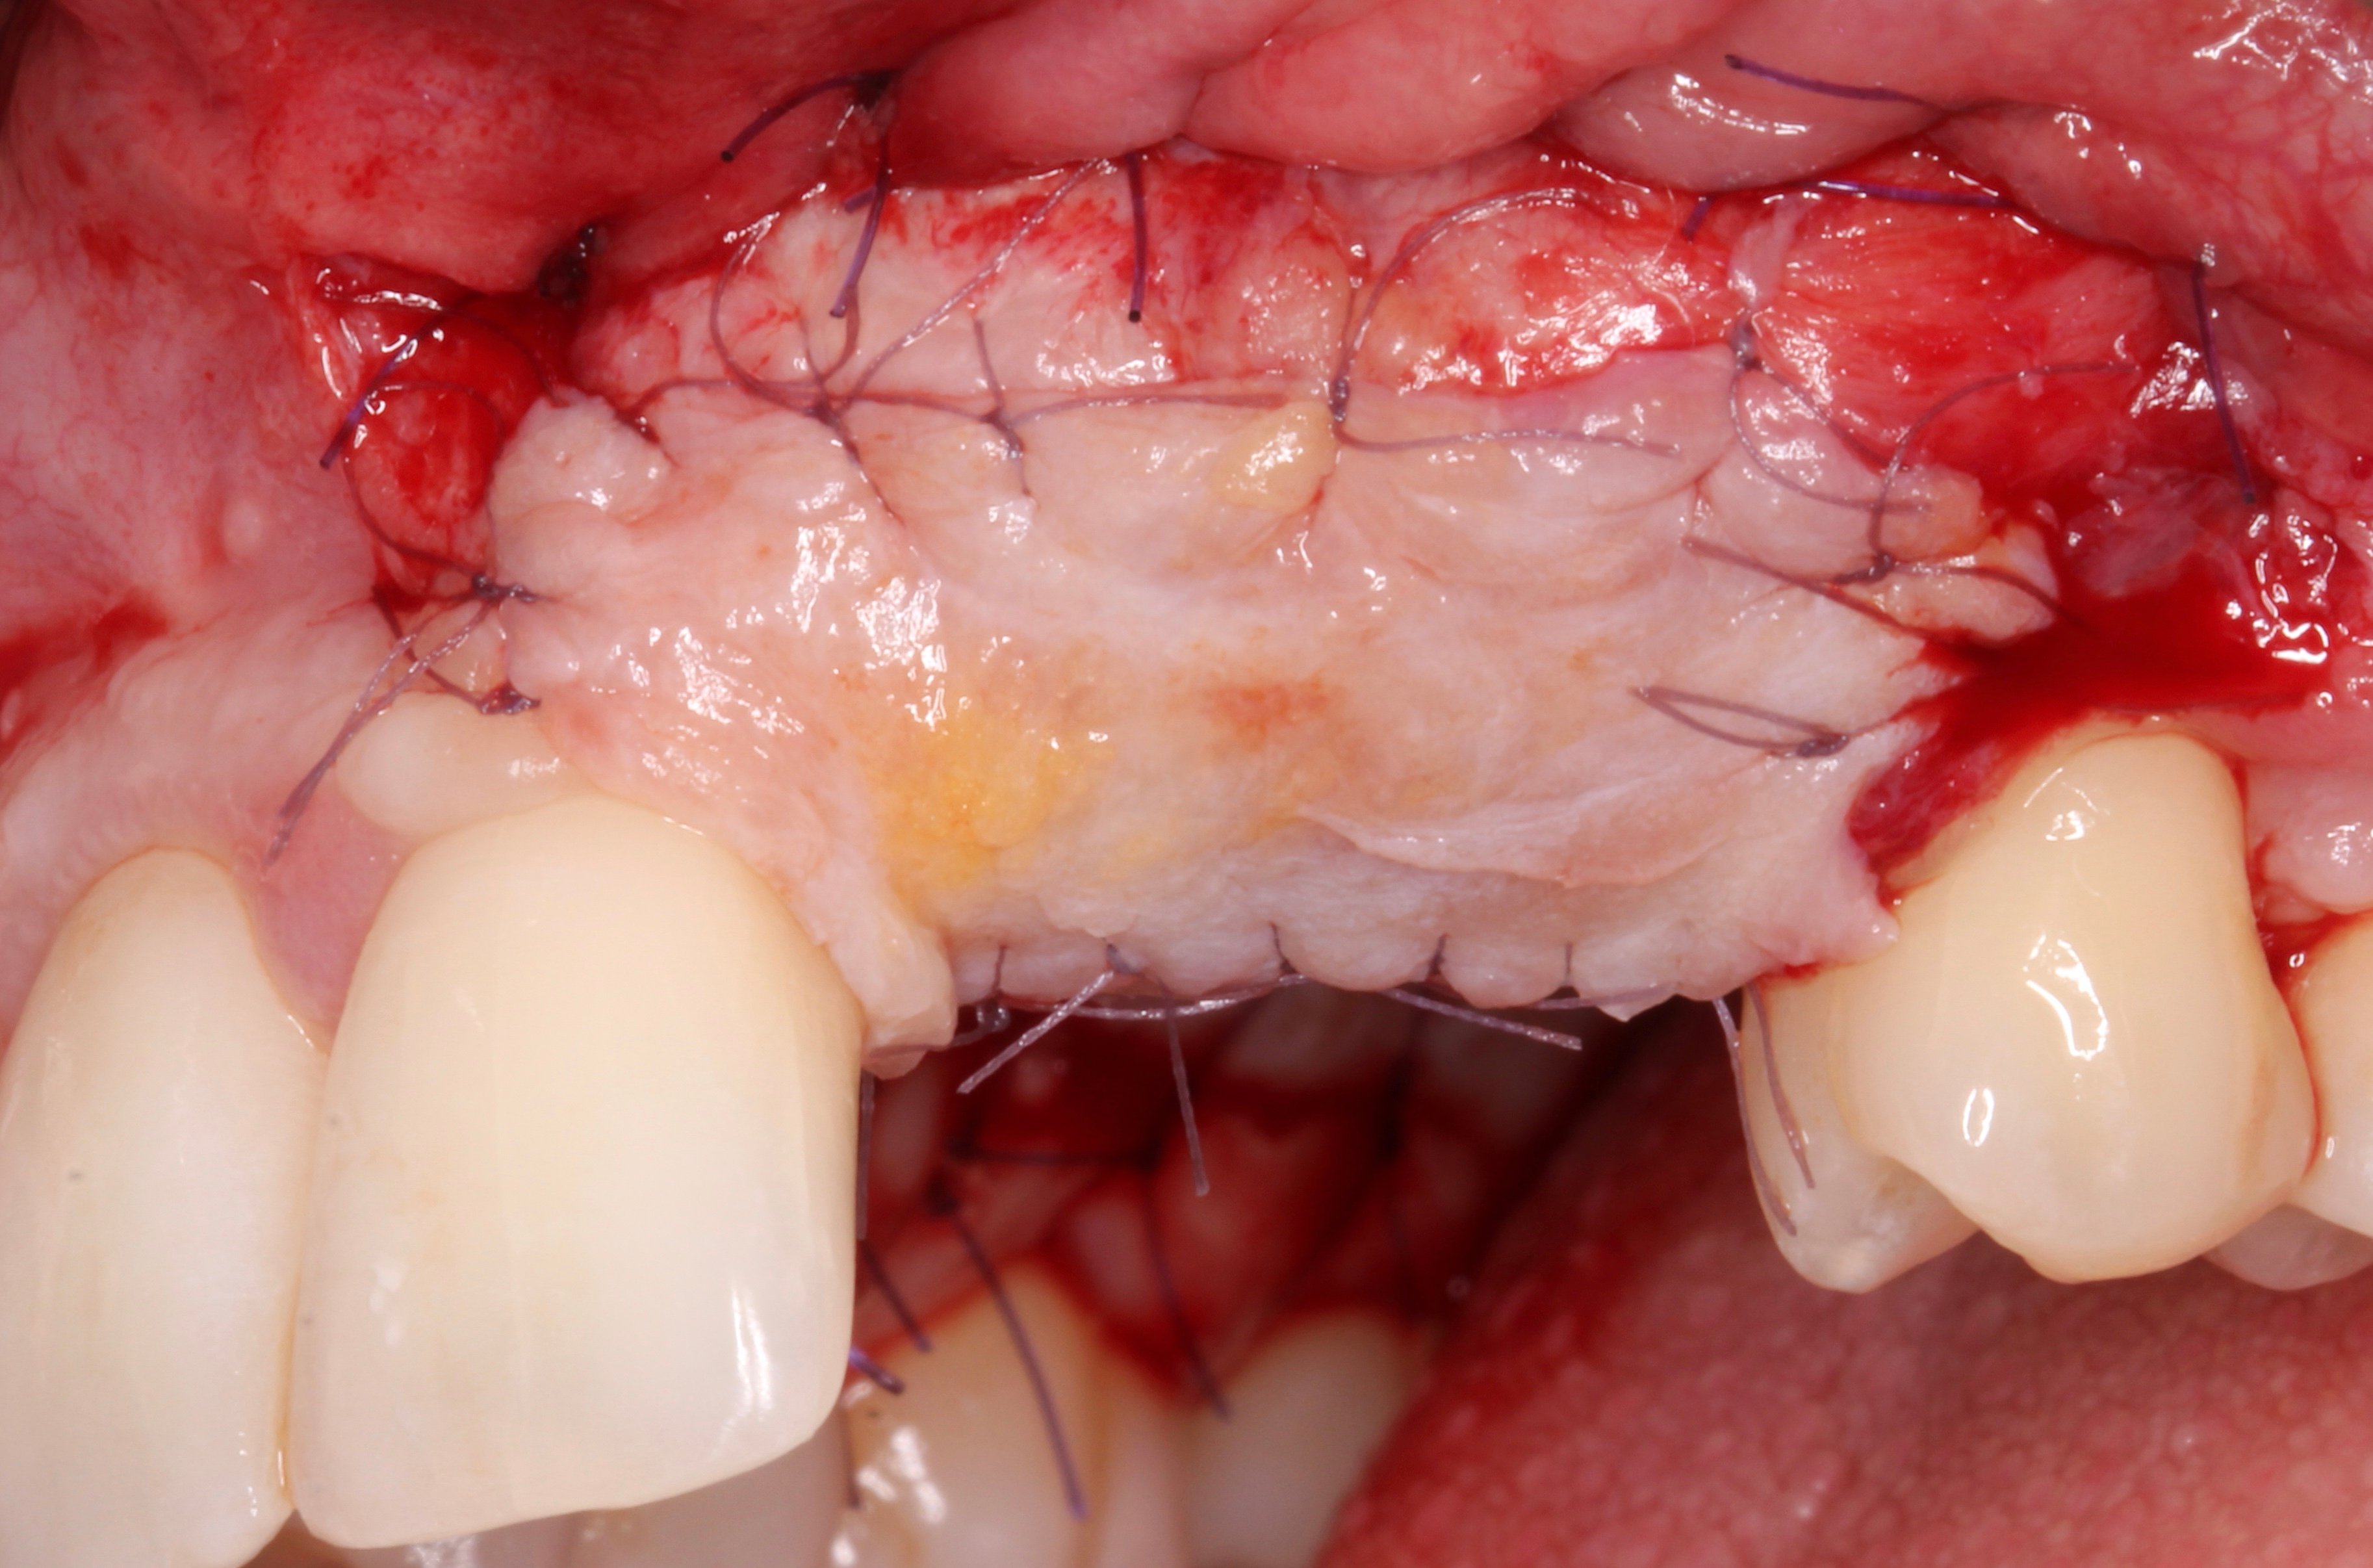

- 3 months later: (which turned out to be 2 years later because the patients was treated and failed elsewhere): 3D guided bone regeneration using 100% autogenous bone and a PTFE, Ti-reinforced NeoGen® membrane which was fixed by Neoss Tacks.

1 NeoGen Ti-Reinforced PTFE Membrane.